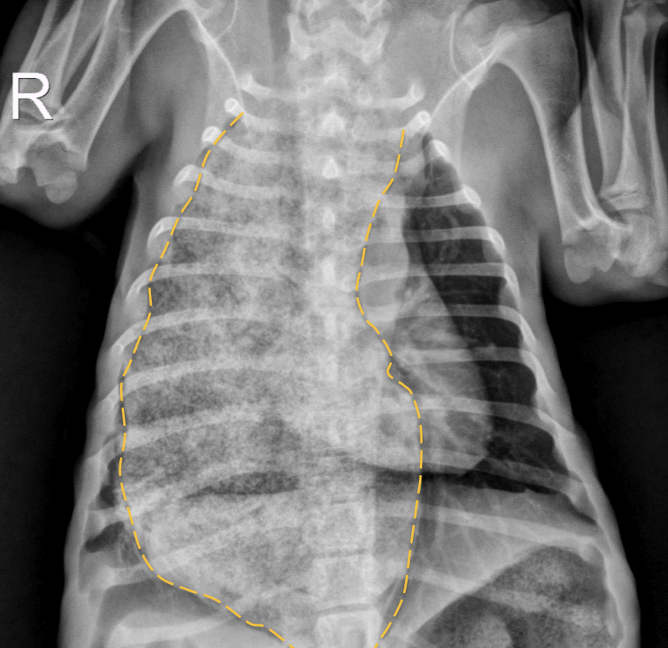

Juvenile idiopathic megaesophagus